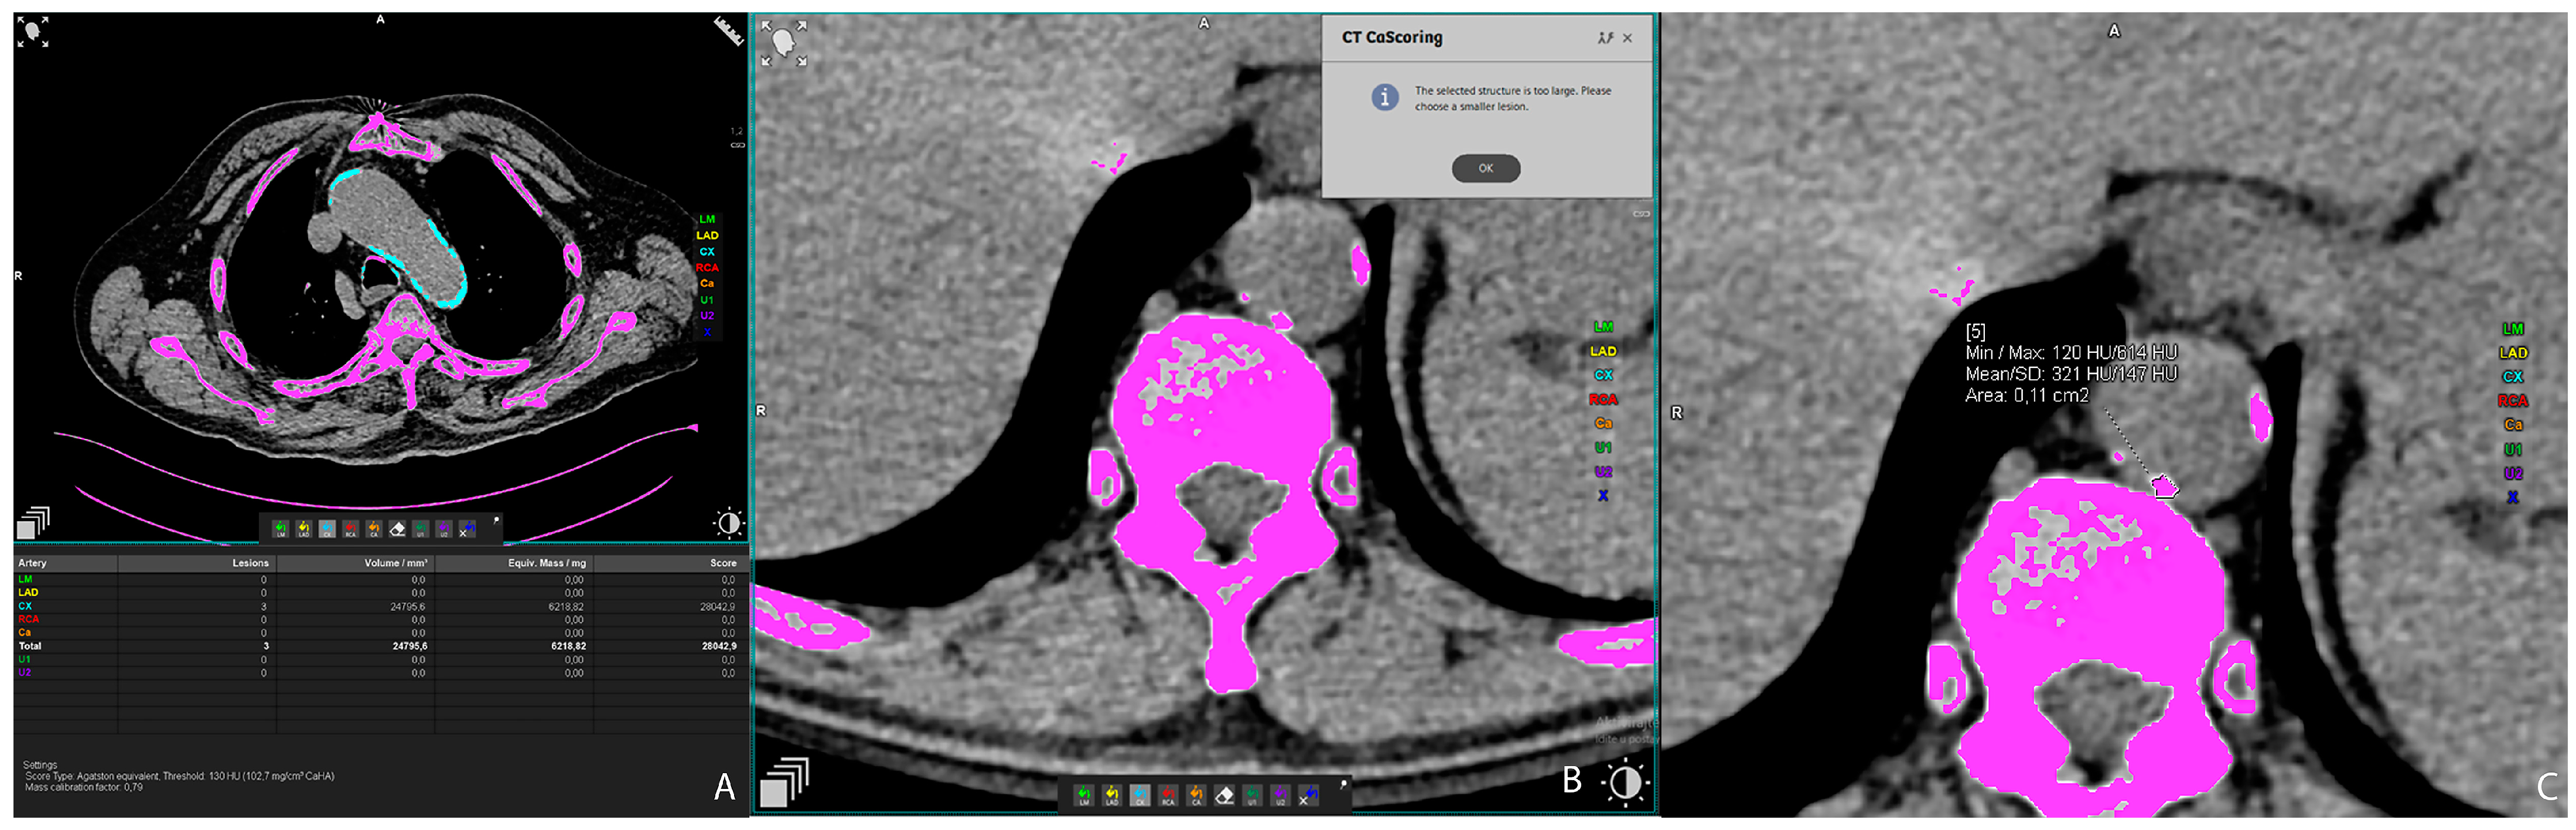

2.2. Vascular Calcification Measurement

Vascular calcifications were measured by trained radiologists using the Siemens (Munich, Germany) Syngovia post-processing tool “Ca Scoring”, which estimates calcifications on native CT scans. The tool is routinely used for coronary artery calcifications with Agatston score calculation. Each researcher passed training prior to the measurements. The procedure was as follows: on the native/pre-contrast scans, each calcification of the thoracic and abdominal aorta and both renal arteries was manually labeled (Figure 1A) and added up to the total volume of calcification of each artery. If the vascular calcifications were too close to the bone structures (spine) or were extending into an adjacent artery (for example thoracic into abdominal aorta), the freehand regions of interest (ROIs) on all scans where the lesion extended were used to delineate calcifications of interest and calculate calcification volume (Figure 1B,C). Finally, the volume of calcification within each artery was expressed in mm3 [22].

Figure 1. Representative axial CT images showing arterial calcification measurement using syngo.via postprocessing software VB60A_HF08 (A), and freehand ROI measurement of calcification volume (B,C).